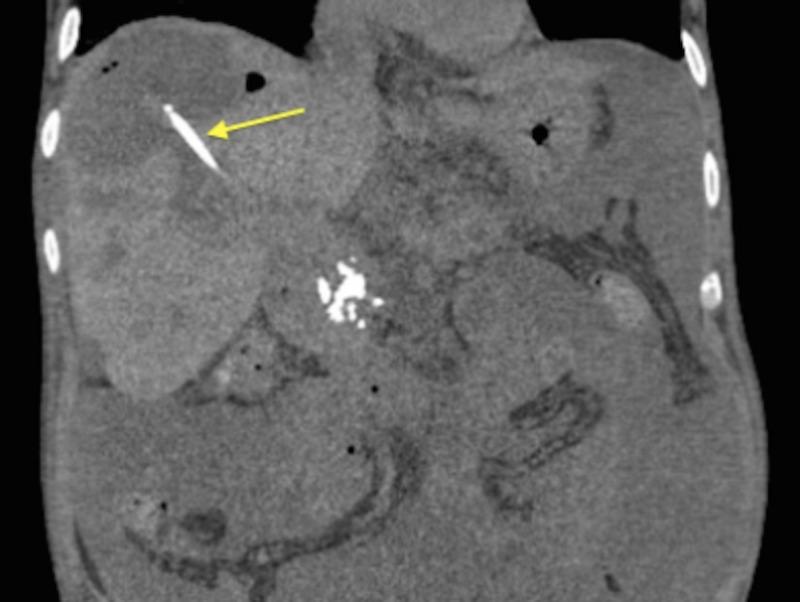

A Case of Candidal Infection of Large Biloma After CT-Guided Liver Biopsy Confirming Autoimmune Hepatitis.

Bilomas are unexpected post-procedural complications of cholecystectomies, hepatic resections, endoscopic retrograde cholangiopancreatography, and-rarely-liver biopsies. While uncommon, this should remain high on the differential in a patient presenting with sudden postop sepsis even in the absence of significant liver injury. Diagnosis involves coordination between interventional radiology, gastroenterology, and internal medicine. This involves a precise clinical history, invasive radiological techniques, and advanced interventional endoscopic solutions for diagnosis and treatment. This is a case of a biloma that occurred as a consequence of a post-hepatic biopsy and resulted in fungal infection, rather than its more common bacterial counterpart. Due to the unusual circumstances, a more circuitous route to the correct diagnosis and treatment was undertaken.